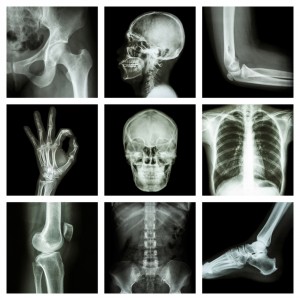

An X-ray is a diagnostic test that images bones by shooting an X-ray beam through the body. The calcium in bones blocks penetration of the X-ray beam and the image of the bones is picked up as a shadow on a film positioned on the other side of the patient. X-rays provide for excellent bony detail because bone consists mainly of calcium. X-rays of the spine can be used to diagnose tumors, fractures, and spinal misalignment. However, discs and nerve roots do not have any calcium, so an X-ray does not capture an image of these structures. An X-ray cannot be used to diagnose lumbar disc herniation or other causes of nerve pinching.

X rays are electromagnetic radiation that differentially penetrates structures within the body and creates images of these structures on photographic film or a fluorescent screen. These images are called diagnostic x rays.

X rays pass easily through air and soft tissue of the body. When they encounter more dense material, such as a tumor, bone, or a metal fragment, they are stopped. Diagnostic x rays are performed by positioning the part of the body to be examined between a focused beam of x rays and a plate containing film. This process is painless. The greater the density of the material that the x rays pass through, the more rays are absorbed. Thus bone absorbs more x rays than muscle or fat, and tumors may absorb more x rays than surrounding tissue. The x rays that pass through the body strike the photographic plate and interact with silver molecules on the surface of the film.

Once the film plates have been processed, dense material such as bone shows up as white, while softer tissue shows up as shades of gray, and airspaces look black. A radiologist, who is a physician trained to interpret diagnostic x rays, examines the pictures and reports to the doctor who ordered the tests. Plain film x rays normally take only a few minutes to perform and can be done in a hospital, radiological center, clinic, doctor's or dentist's office, or at bedside with a portable x-ray machine.